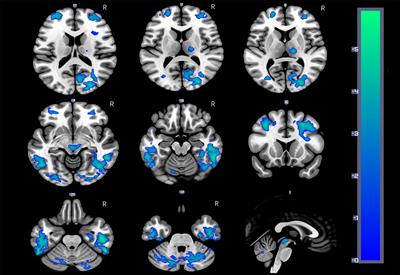

A Beginner's Guide to Arterial Spin Labeling (ASL) Image Processing

in Neuroradiology